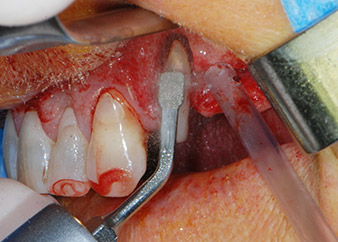

След един месец, в деня на операцията, болката и възпалението в зъб 24 е минимално, но подвижността в Miller class 2 е на лице. След отваряне на ламбата и почистването на периапикалната и перирадикуларната тъкани, обхватът на костния дефект стана очевиден (Фиг. 2 и 3).

В букалния корен, цялата вестибуларна и дистална кост липсва. Захващането е значително ограничено до палатиналния корен, подчертавайки предварително лошата прогноза. Зъб 27 също откри намалено хоризонтално захващане и минимално апикално разреждане (Фиг. 1) без клинични симптоми.

тотална загуба на кост и захват

Фиг. 2 и 3: След повдигане на ламбото, един месец след ендодонтския преглед и прилагане на цялостна периодонтална терапия в цялата уста, букалният корен на зъб 24 разкри тотална загуба на кост и захват.

Въпреки това, ние се придържахме към първоначалния си план да запазим и двата зъба като абатмънти за временен мост по време на 6-месечната остеоинтеграция на имплантите. При повторна интервенция, ситуацията трябва да се преразгледа. Първо, в опит да се овладее ендо-перио проблема, останалата повърхност на зъба е внимателно обработена с пиезохирургично оборудване (Piezomed, W&H, използван с накрайник S1 под формата на шпатула, първоначално проектиран за ерозия на латералната синусна стена) (Фиг. 4).